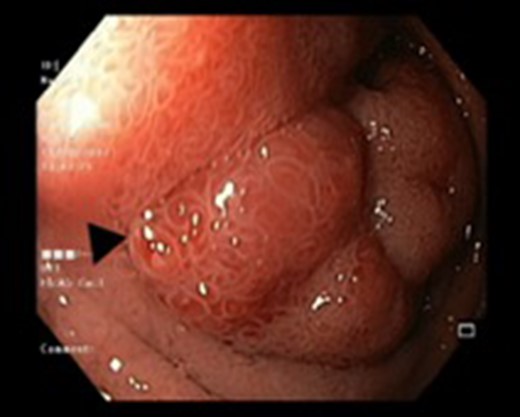

There were three males and one female who had Brunner’s gland hyperplasia as the pathological finding in their surgical specimens following operations for duodenal lesions. Their mean age at presentation was 39.7 ± 10.14 (range: 30–52) years and their presenting features were abdominal pain in two patients, vomiting (2), and upper gastrointestinal bleeding (2). The duration of their symptoms varied between 4 days and 4 years prior to presentation. All patients underwent an upper gastrointestinal endoscopy (Figs 1 and 2) and abdominal computed tomography(Figs 3 and 4) scans as part of their evaluation. The details of patient presentation, evaluation, surgical procedure and outcomes are described in Table 1.

Endoscopic view of a submucosal mass in the second part of the duodenum.

| Case 1 | 30/M | 3 months | Vomiting, Malena | Well defined rounded hypodense submucosal lesion in second part of duodenum (Fig. 1) | Smooth mucosal bulge likely due to submucosal lesion in D2 with difficulty in negotiating scope beyond (Figs 2 and 3) | Normal duodenal mucosal fragments with mild lympho-mono nuclear cell infiltrate in the lamina propria | Pancreaticoduodenectomy | 2 | 2 days | 6 |

Endoscopy can localize the lesion; however, biopsies are usually negative. Only a deep endoscopic or a surgical biopsy provides adequate tissue because the Brunner’s gland proliferations are usually covered by normal mucosa [10] (Figs 6 and 7). It is prudent to include a Brunner gland hyperplasia in a differential diagnosis while evaluating a duodenal mass, since it has varied presentation and bleeding is a common clinical sign masquerading other gastrointestinal conditions, e.g. gastrointestinal stromal tumours.